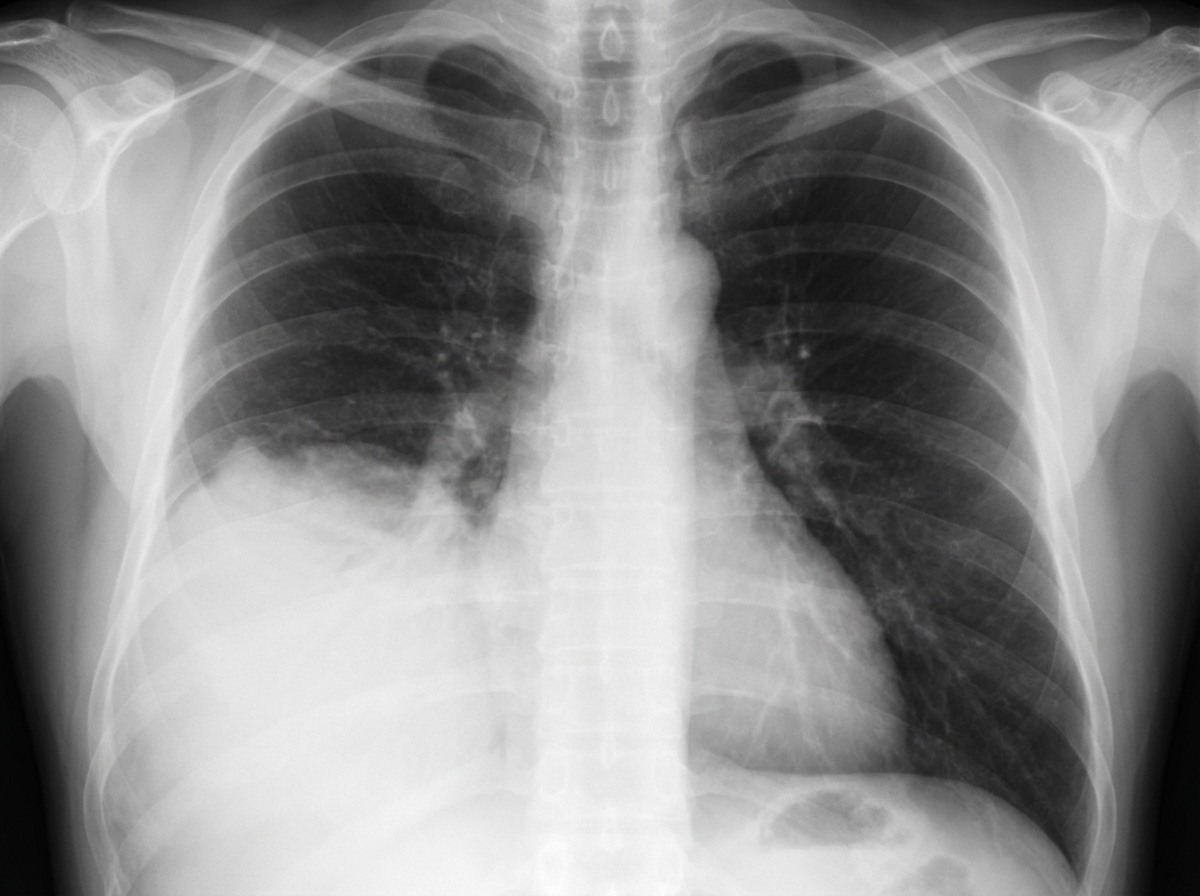

A 40-year-old male presented to the OPD with fever and breathlessness. His X-ray is shown below. What is the most probable diagnosis?

Explanation: ***Pneumonia*** - Fever and breathlessness with **consolidation** and **air bronchograms** on chest X-ray are classic features of pneumonia. - The acute presentation with respiratory symptoms strongly supports **community-acquired pneumonia** rather than chronic conditions. *Tuberculosis* - Typically presents with **upper lobe cavitation** or **miliary pattern** on chest X-ray, not consolidation. - Usually has a more **chronic course** with night sweats, weight loss, and hemoptysis over weeks to months. *Pleural effusion* - Chest X-ray would show **meniscus sign** and **homogeneous opacification** obscuring lung markings. - Clinical presentation includes **dull percussion note** and **reduced breath sounds** rather than consolidation features. *Bronchogenic carcinoma* - X-ray findings include **lung mass**, **hilar enlargement**, or **collapse/consolidation** due to obstruction. - Typically presents with **chronic cough**, **weight loss**, and **hemoptysis** rather than acute fever and breathlessness.